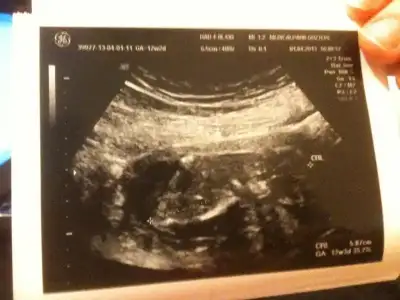

dr soylemeden siz gorun genital nub teorisi ( bebegin cinsiyeti)

anlayan arkadaşlar sizce nub belli mi cinsiyet konusunda bir fikriniz var mı?

11.haftada dr. cinsiyetine önce kız dedi, sonra pipi gördüm dedi, sonra da kordon olabilir dedi, yani bilemedi, orkidem kız demişti. 16.haftada başka bir dr. %98 kız dedi.

18.haftada kendi doktorum erkek dedi ve pipiyi gösterdi.

lakin biz emin olamadık, kafamız karıştı.

21.haftada ayrıntılı ultrason için gittiğimiz perinatoloji uzmanı (prof.) erkek dedi, biz de gördük pipiyi.